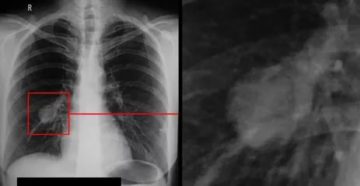

Операции на легких Парным органом, который обеспечивает весь человеческий организм кислородом, являются легкие. Нередко именно…

Как подготовиться к прохождению флюорографии С помощью снимка лёгких, полученного в результате флюорографии, врачи могут…